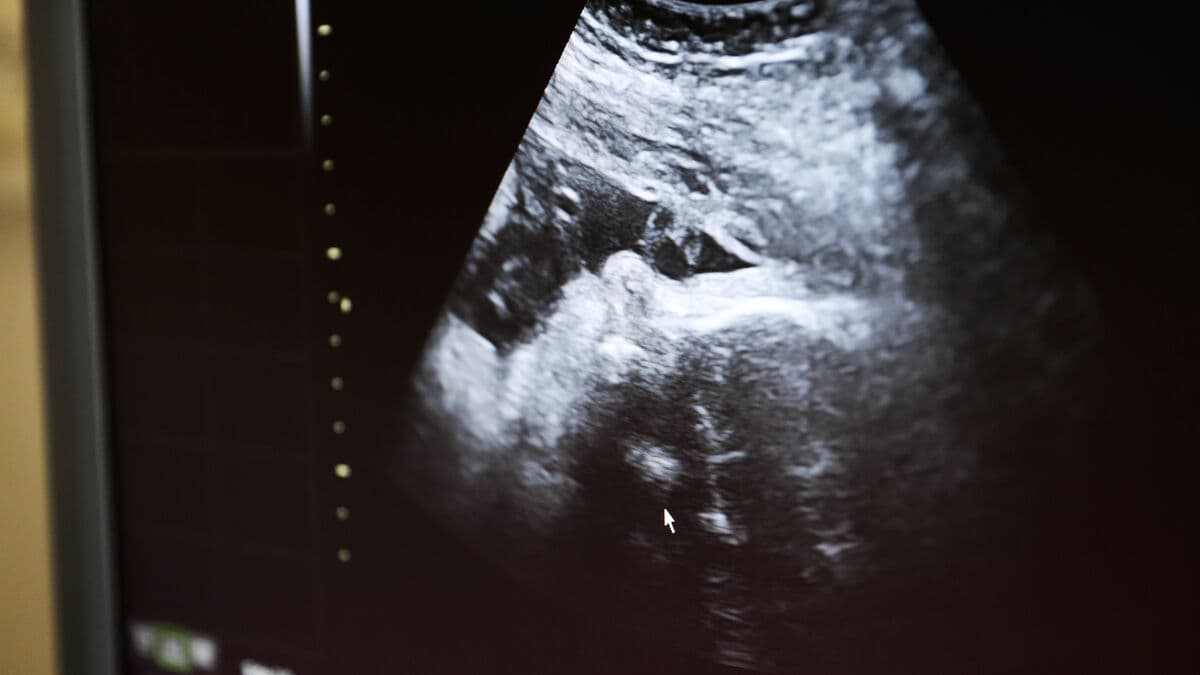

According to an SVT investigation, several regions are planning to replace KUB with the more accurate NIPT. KUB is currently used to examine the likelihood of chromosomal abnormalities in the fetus. When KUB shows an abnormality, NIPT is often used as a follow-up.

Both tests have advantages and disadvantages. NIPT is more accurate, but involves higher costs. At the same time, KUB can detect abnormalities that NIPT cannot.